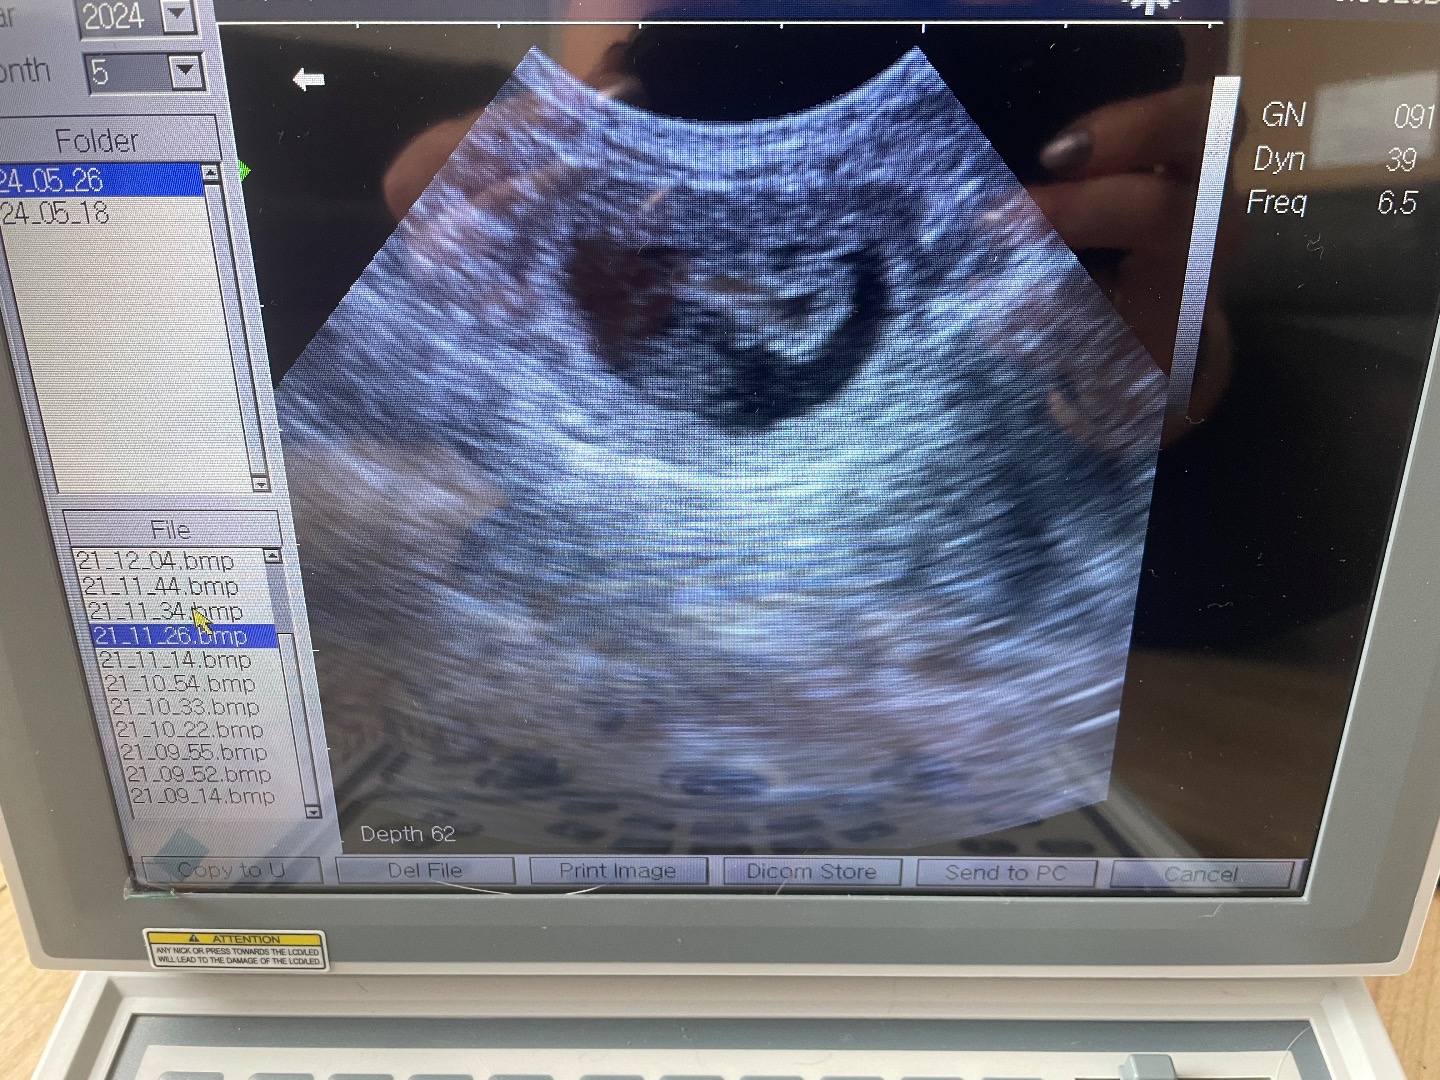

Following miscarriage of her entire litter, Fenn’s owner was understandably nervous during her subsequent pregnancy so we paid extra attention to Fenn throughout. This was a reassurance scan at full